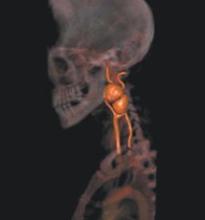

Heart disease and stroke are the first and third leading causes of death in the U.S. Atherosclerosis is the common pathological process underlying myocardial infarction, stroke and other occlusive vascular diseases. Atherosclerosis has a long latent period between early phases of the disease and the manifestation of clinical symptoms. Thus, there is an opportunity for primary prevention if patients can be identified before the first clinical event.